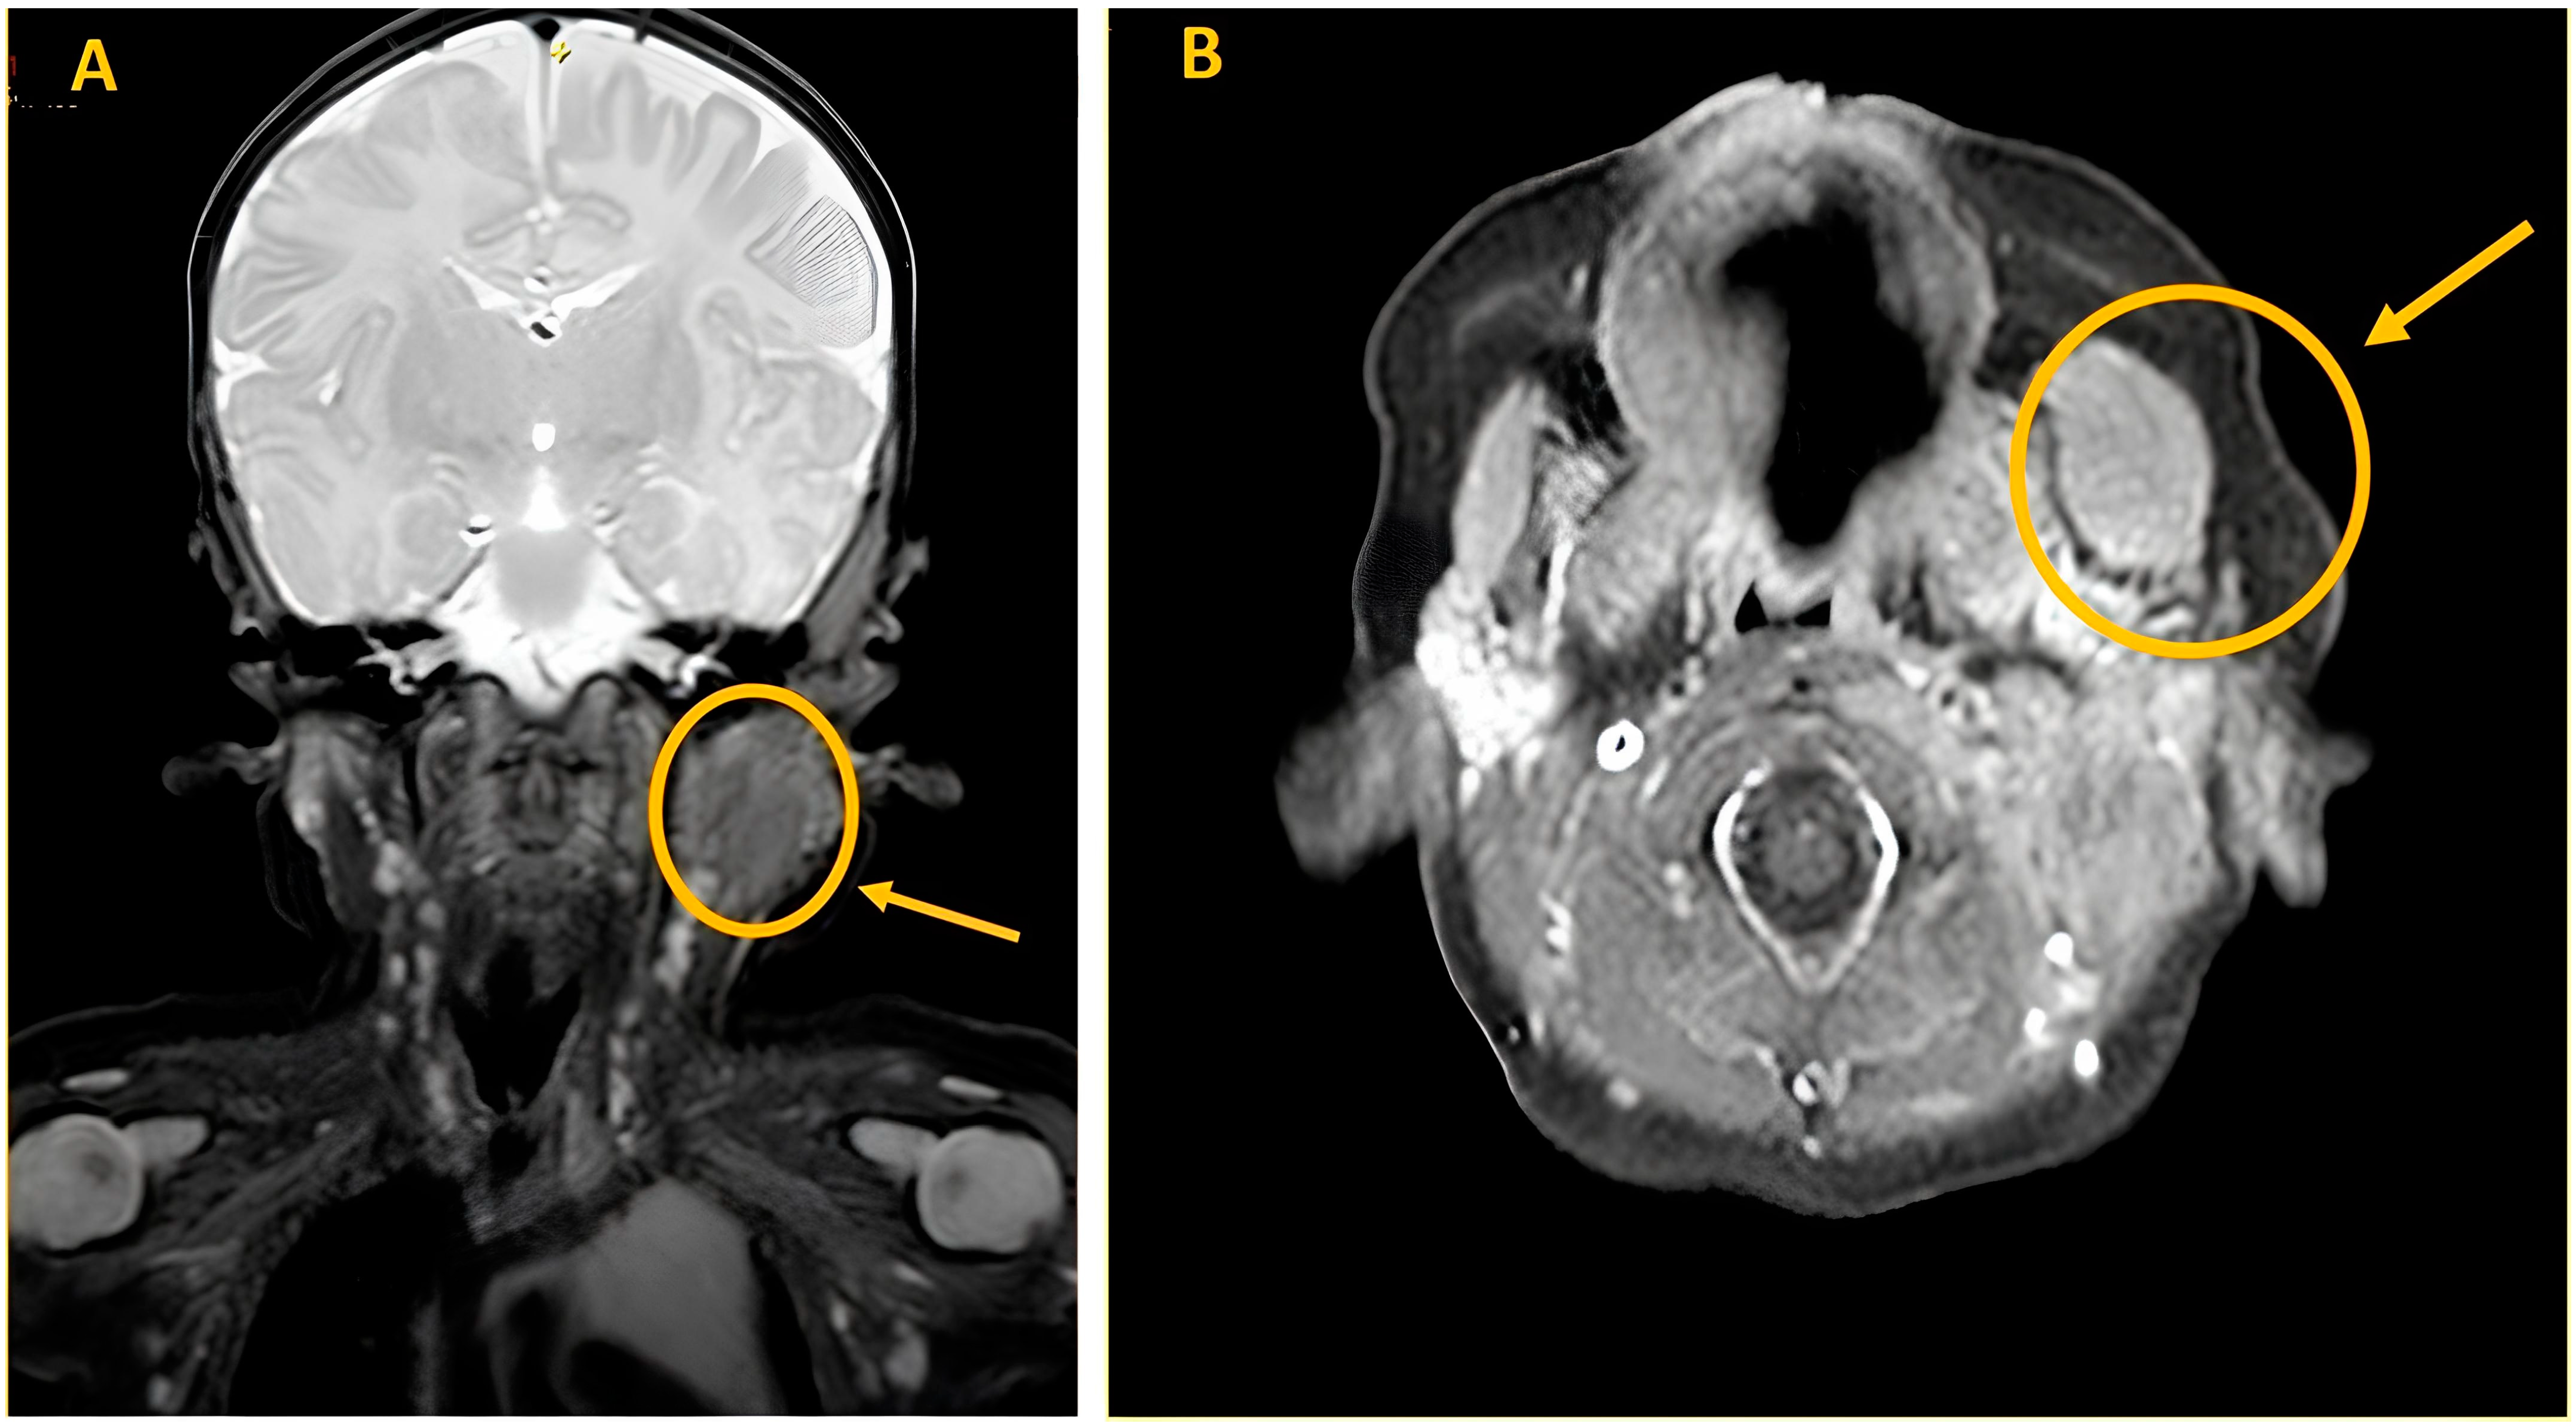

A Magnetic Resonance imaging (MRI) of the soft tissues was performed and showed an enlargement in the context of the left masseter muscle (20 mm × 15 mm × 21 mm). The lesion appeared minimally hyperintense in T2 sequences and isointense in T1 sequences with negative contrast enhancement. The MRI study confirmed a thickened proximal SCM (13 mm × 14 mm × 31 mm), as shown in Figure 3.

Figure 3. Head and neck MRI. Examination performed before and after intravenous bolus administration of 1 ml of paramagnetic contrast medium, such as Dotarem (gadoteric acid) 0.5 mmol/mL. (A) Coronal image T2 dixon: Fusiform dilation of the left masseter muscle (20 mm × 15 mm × 21 mm) with minimal, homogeneous hyperintensity in T2 signal. Fusiform swelling at the level of the cranial slope of the left sternocleidomastoid muscle (13 mm × 14 mm × 31 mm). (B) Intravenous contrast-enhanced axial image T1 dixon: Homogeneous isointensity of the signal in T1 with no perifocal edema or pathological enhancements after contrast administration.